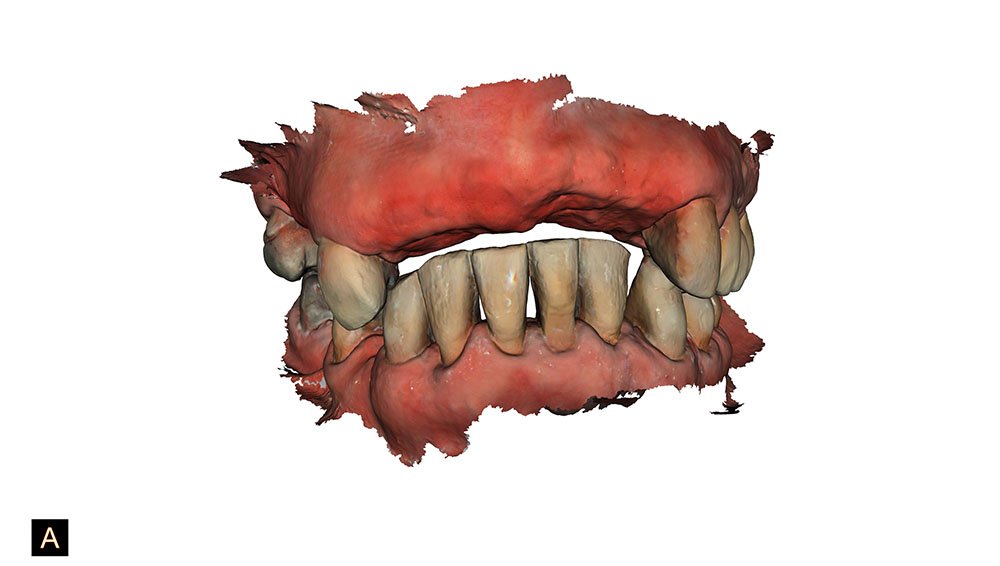

Neste caso clínico, a paciente estava insatisfeita justamente com a estética e a mastigação de sua atual condição bucal. Por conta de apresentar diversos dentes comprometidos, foi indicada a confecção de reabilitação oral com prótese do tipo protocolo bi maxilar sobre implantes dentários.

Inicialmente, foi identificado um sorriso invertido e uma projeção dos elementos dentais para além da linha molhada do lábio.

Através do escaneamento intraoral, foi realizado o planejamento das cirurgias guiadas (ODONTOPLANNING-BRASIL).